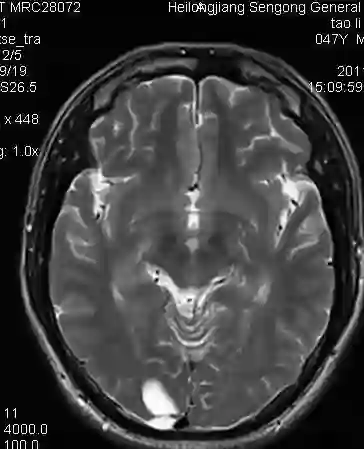

人工智能在医学中的应用目前是一个热门的话题,医学影像图像如MRI的肿瘤等病变部位检测和识别对于诊断的自动化,提供优质的治疗具有重要的意义。

肿瘤检测